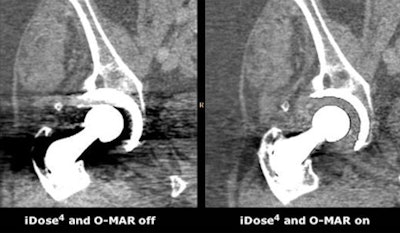

![]() |

| Image courtesy of Philips Healthcare. |

Philips' Premium Package includes iDose4, the fourth generation of Philips' iDose iterative reconstruction technique, and technology to reduce artifacts from large metal implants. Called O-MAR (metal artifact reduction for orthopedic implants), the algorithm reduces artifacts that can result in a loss of anatomical information, impeding visualization of tissue and critical structures, according to the company.